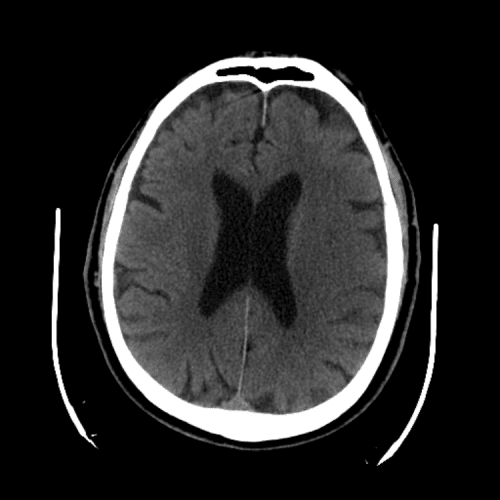

Non-traumatic Head CT Cases

Classic Cases

Includes classic examples of cases commonly seen on call.

PCA infarct

Case #2